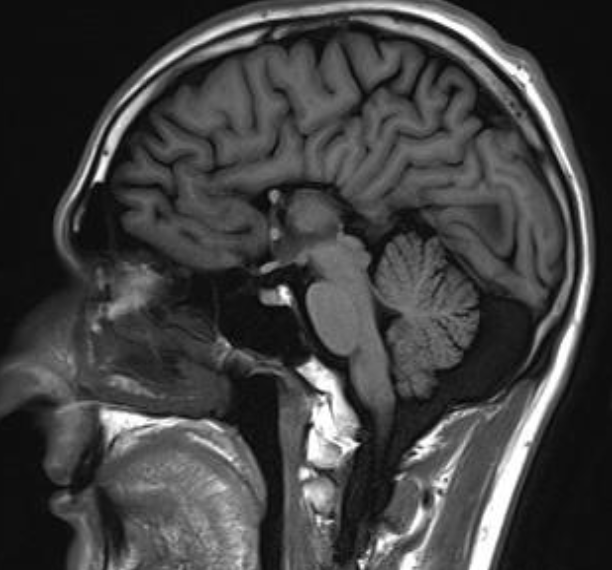

Agenesis of corpus callosum

Sagittal T1 MRI brain